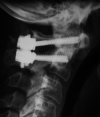

C1-2 polyaxial screw-rod fixation is a relatively new technique. While recognizing the potential for inadvertent vertebral artery injury, there have been few reports in the literature outlining all the possible complications. Aim of this study is to review all cases of C1 lateral mass screws insertion with emphasis on the evaluation of potential structures at risk during the procedure. We retrospectively reviewed all patients in our unit who had C1 lateral mass screw insertion over a 2-year period. The C1 lateral mass screw was inserted as part of an atlantoaxial stabilization or incorporated into a modular occiput/subaxial construct. Outcome measures included clinical and radiological parameters. Clinical indicators included age, gender, neurologic status, surgical indication and the number of levels stabilized. Intraoperative complications including blood loss, vertebral artery injury or dural tears were recorded. Postoperative pain distribution and neurological deficit were recorded. Radiological indicators included postoperative plain radiographs to assess sagittal alignment and to check for screw malposition or construct failure. A total of 18 lateral mass screws were implanted in 9 patients. There were three male and six female patients who had C1 lateral mass screw insertion in this unit. Two patients had atlantoaxial stabilization for C2 fracture. There were four patients with rheumatoid arthritis whose C1 lateral mass screws were inserted as part of an occipitocervical or subaxial cervical stabilization. There was no vertebral artery injury, no cerebrospinal fluid leak and minimal blood loss in all patients. Three patients developed postoperative occipital neuralgia. This neuralgia was transient, in one of the patients having settled at 6-week follow-up. In the other two patients the neuralgia was unresolved at time of latest follow-up but was adequately controlled with appropriate pain management. Postoperatively no patient had radiographic evidence of construct failure and all demonstrated excellent sagittal alignment. It has been reported that the absence of threads on the upper portion of the long shank screw may protect against neural irritation. However, insertion of the C1 lateral mass screw necessitates careful caudal retraction of the C2 dorsal root ganglion. The insertion point for the C1 lateral mass screw is at the junction of the C1 posterior arch and the midpoint of the posterior inferior part of the C1 lateral mass. Two patients in our series suffered occipital neuralgia post-insertion of C1 lateral mass screws. This highlights the potential for damage to the C2 nerve root during C1 lateral mass screw placement.